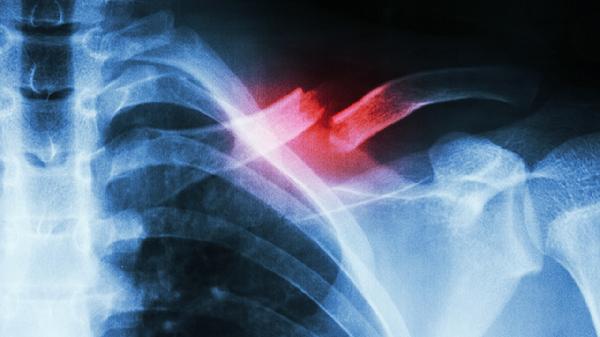

多发性肋骨骨折严重吗 多发性肋骨骨折的几个影响须知

多发性肋骨骨折是否严重需根据损伤程度判断,可能引发疼痛、呼吸困难、肺部感染等并发症,严重时可危及生命。主要影响包括剧烈胸痛、反常呼吸运动、血胸或气胸、肺部感染、迟发性内脏损伤。

2、反常呼吸运动

三根以上相邻肋骨双处骨折时,胸壁失去支撑形成浮动胸壁,吸气时骨折区凹陷、呼气时凸出。需紧急行肋骨内固定术恢复胸廓稳定性,术后配合呼吸训练器改善肺功能。